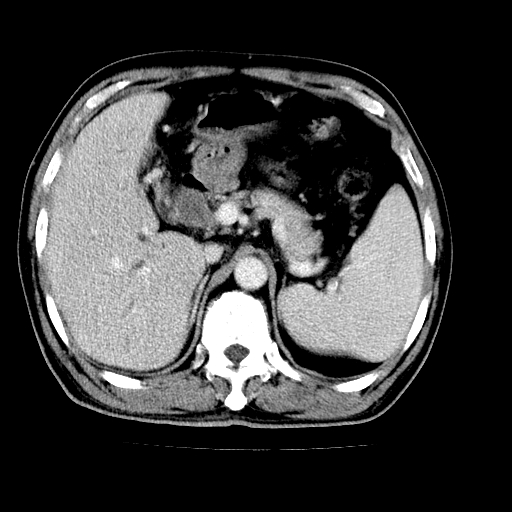

男,66岁,上腹部不适、黄染一周。彩超示:肝左叶占位,肝内胆管扩张,胆总管扩张,胆总管占位?

肝左叶不规则软组织肿块影,边缘不规整邻近肝实质受累分界不清;肝内胆管(左叶)明显扩张成“软藤状”,诊断:肝左叶胆管细胞癌。

左叶胆管细胞癌累及胆总管,门脉左支受侵,慢性胆囊炎胆结石,左肾小囊肿

肝左叶不规则软组织肿块影,边缘不规整邻近肝实质受累分界不清;肝内胆管(左叶)明显扩张成“软藤状”,诊断:肝左叶胆管细胞癌。胆囊钙乳症。

胆囊缩小,其内胆汁浓缩,也提示梗阻部位应该位于胆囊管起始部以上或是胆囊管受累及,支持肝外胆管癌。